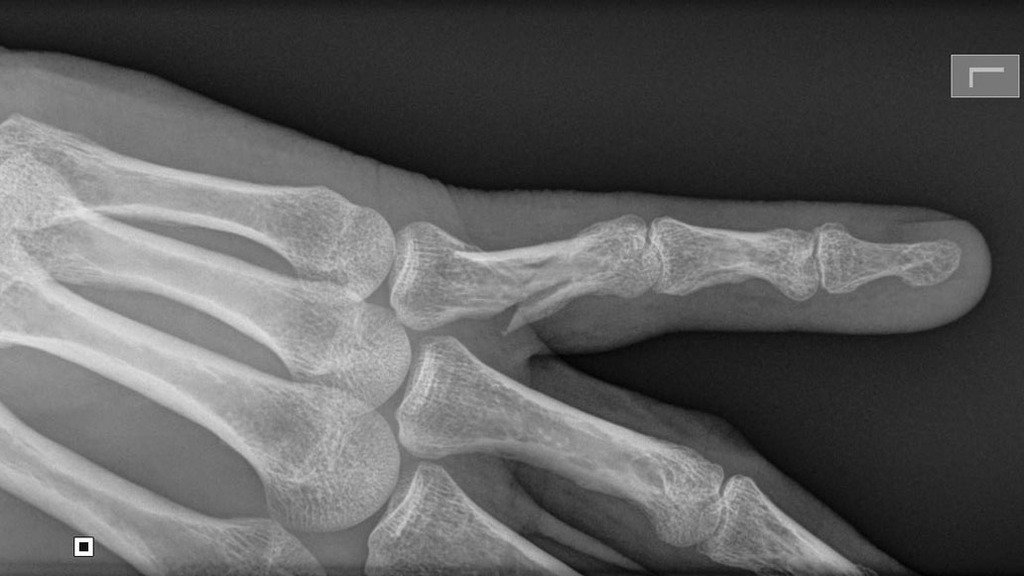

X-rays confirmed that it was not only dislocated but broken. The doc straightened it out and strapped it up. With the help of some powerful pain-killers I made it through the next week. But the orthopod had some bad news: my finger was healing in the wrong direction. So more x-rays:

X-Ray

Yup, the break had not closed. There was only one thing for it: the bones needed to be re-broken and pinned in the right direction. This required an operation which was quite interesting since I could watch the surgeon drill and pin the bones on the monitor. (Yes, it was a local anesthetic.)